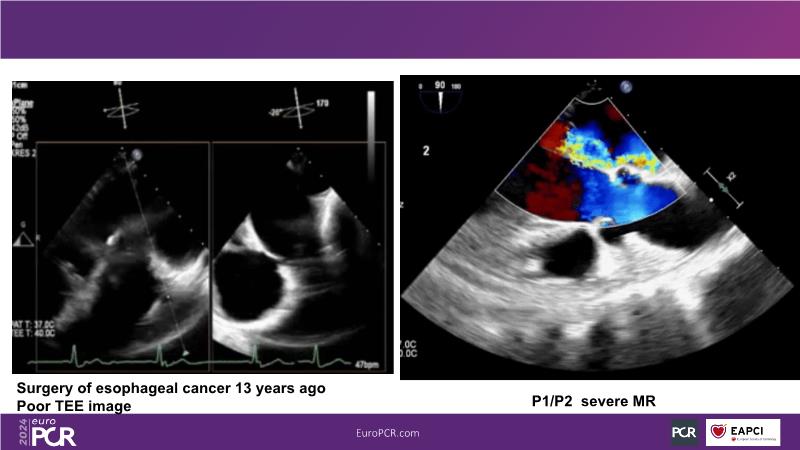

Watch this session to gain insights into the clinical evidence of mitral TEER therapy for the Asian population, learn techniques for implanting a MitraClip in patients with challenging anatomy, and understand how to use the four clip sizes for optimal outcomes. The session also covers educational aspects of clipping in dextrocardia, the benefits of reserve bending of the transseptal needle for tenting and puncture, new steering maneuvers for dextrocardia patients, and the importance of understanding anatomy and collaborating closely with the echo team for success.